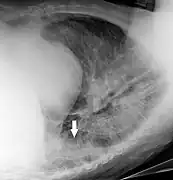

In projectional radiography, visual artifacts that can constitute disease mimics include jewelry, clothes and skin folds.[7]

A hip fracture (black arrow) next to a skin fold (white arrow).

Bed sheets looking like lung opacities on a chest radiograph